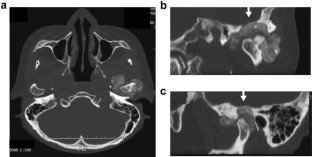

A case of tophaceous pseudogout (i.e., calcium pyrophosphate dihydrate crystal deposition disease) in the temporomandibular joint (TMJ) extending into the cranium is reported. A 59-year-old woman was referred to hospital with swelling and pain in the left cheek, and with trismus. Computed tomography imaging revealed a large, granular, calcified mass surrounding the left condylar head, partly destroying the cortex of the condylar head, and extending into the cranium by destroying the glenoid fossa. Magnetic resonance imaging revealed that the soft-tissue mass was of low-signal intensity on T1- and T2-weighted images, and was enhanced after intravenous injection of gadolinium. The mass was clinically and radiographically suspected to be a neoplastic lesion or a synovial osteochodromatosis. However, histological analysis demonstrated that the mass contained granulomatous lesion due to multiple nodular deposits of numerous rod-shaped and rhomboid crystals, which verified the diagnosis of tophaceous pseudogout. The lesion was excised surgically using a preauricular approach. Neither radiographic nor clinical examination demonstrated any signs of mass recurrence in the long-term 8- and 14-year postoperative recall examinations. Tophaceous pseudogout is a rare benign arthropathy that presents with clinical and radiographic features mimicking neoplastic conditions of the TMJ. Therefore, it is recommended that tophaceous pseudogout is considered in the differential diagnosis when a calcified mass lesion of the TMJ is encountered.

Fig. 1